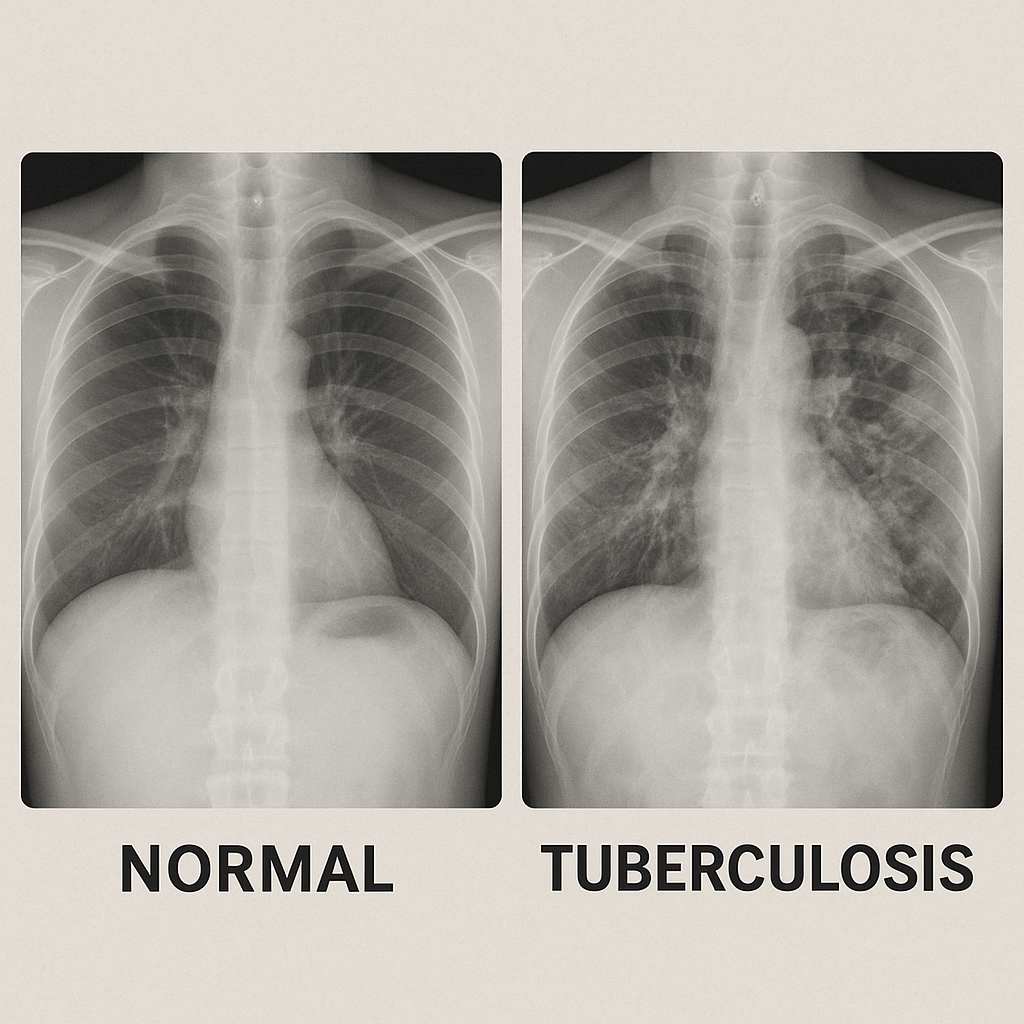

진단은 흉부 X선 검사, 객담검사, 혈액 검사 등을 통해 이루어집니다.